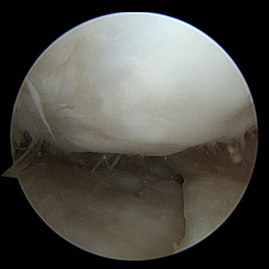

수술적 치료 : 무릎 연골재생술

초기

관절경적 미세천공술(Microfracture)

비교적 작은 연골 결손일 때, 체내 재생을 유도하는 단순하고 부담이 적은 수술입니다.

적응증 (누가 하는가)

- 국소적으로 작은 연골 결손(보통 2~3cm² 이하)

- 나이가 비교적 젊은 환자

- 연골 주변 조직 상태가 비교적 좋은 경우

- 연골이 광범위하게 닳지 않은 초기 연골손상

수술 방법 (어떻게 하는가)

1관절경(내시경)으로 병변 부위 관찰 손상된 연골을 정리

2뼈 표면에 작은 구멍 여러 개를 뚫어 미세천공 시행

3골수에서 재생 세포가 나오도록 유도

4세포들이 굳어져 섬유성 연골(질은 조금 떨어짐)이 새로 채워지는 방식

수술 전후 사례

수술 전

카티스템 수술

수술 후 1년